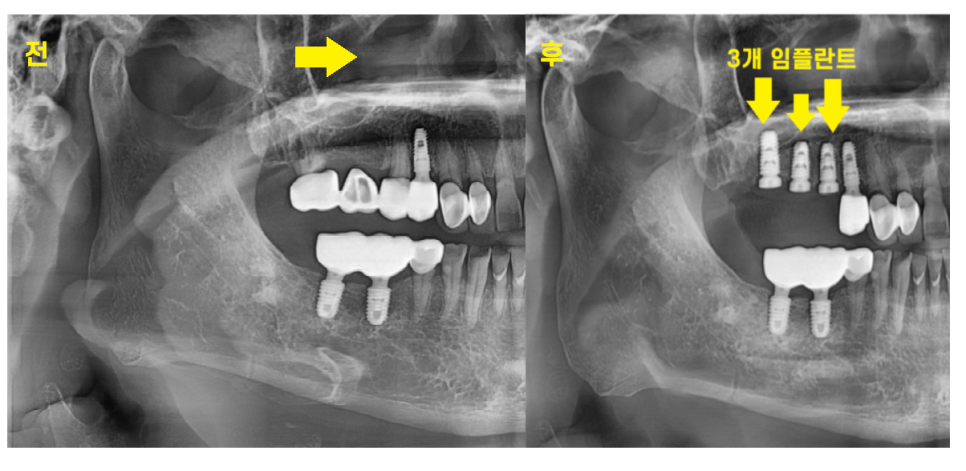

3d-ct를 통해

남아있는 뼈 분석하고 임플란트까지 완료했습니다.

예전에 치아가 빠지고 씌울 때는

2개 치아 -> 3개 머리 브릿지 형태로 하셨지만

20년만에 치료하시는만큼

더 튼튼하게 씹을 수 있도록

치아 개수대로 계획을 잡아드렸습니다.

3개 치아 빠진 개수만큼

고덕동 임플란트

진행해드렸습니다.